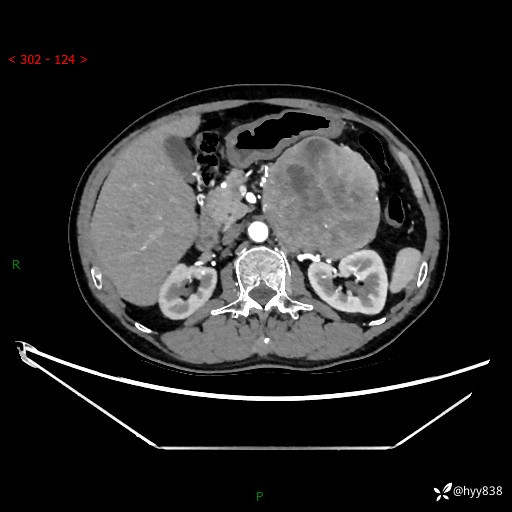

年龄:61岁

主诉:发现腹膜后肿瘤3天

腹部CT平扫+增强(动脉期+静脉期)